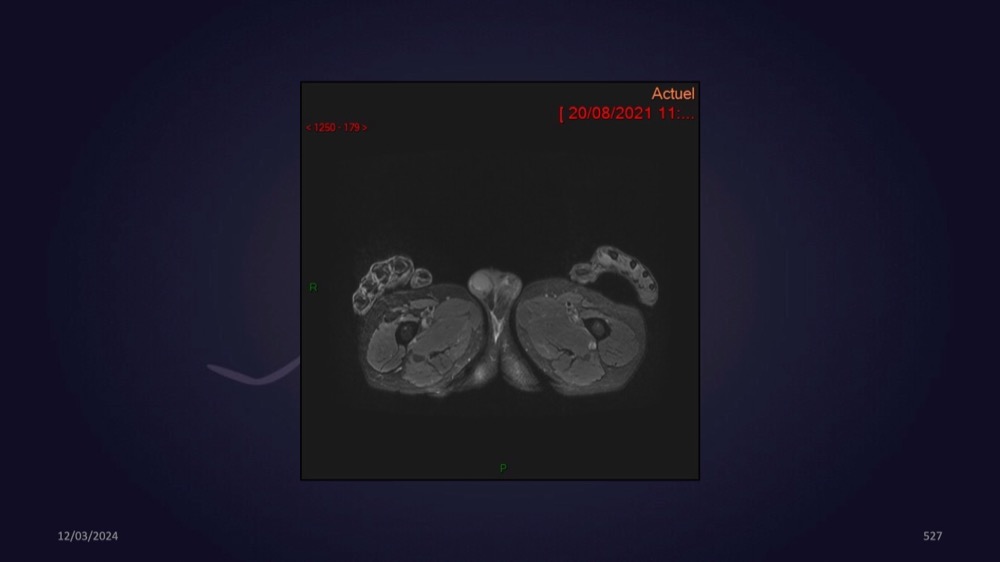

Mezhgani / Dimitri Boulos / Carlier 23/03/2022